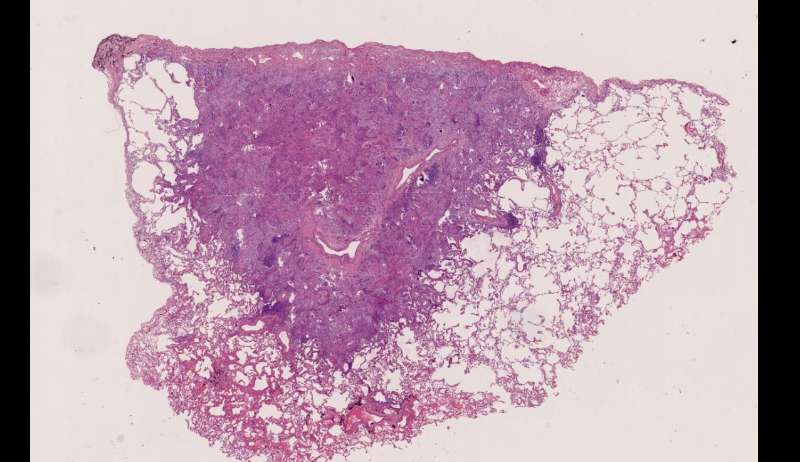

最后发一例化脓性炎症

中性粒细胞很多,此处组织结构破坏

左侧液化,脓肿壁较规则平滑

周围的炎症机化区

破坏力在这里逐渐减弱

逐渐从中性粒细胞转为淋巴细胞为主

周边区:

肺泡内有渗出,逐渐吸收 机化是不是纤维细胞增多看的?王:是的